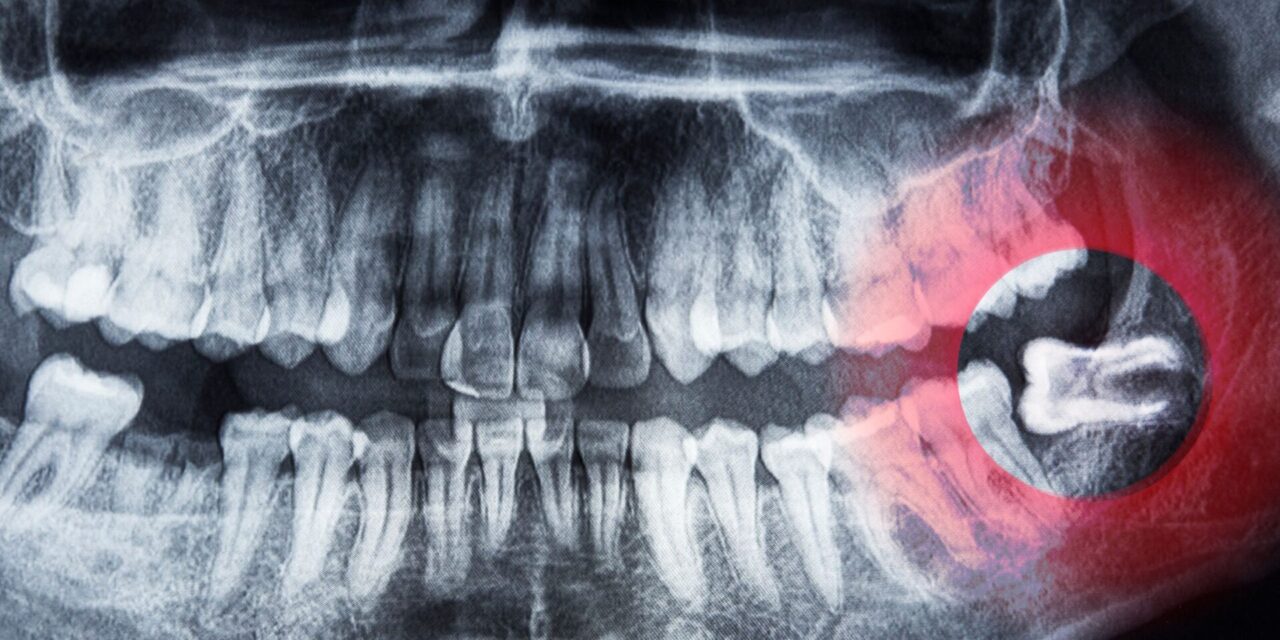

- Diagnóstico previo: Antes de cualquier extracción, se realizará una radiografía (generalmente una ortopantomografía y, en casos complejos, una tomografía CBCT 3D) para evaluar la posición de la muela, su relación con los nervios y las raíces de los dientes adyacentes.

- Tecnología de la clínica: Una clínica moderna debe contar con radiografías digitales de última generación, como la ortopantomografía o el CBCT 3D, que ofrecen imágenes precisas para una planificación detallada de la extracción.